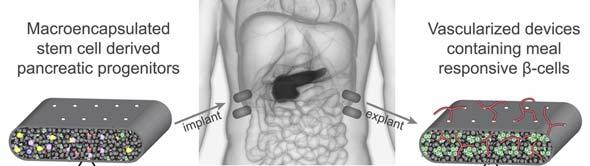

диабет

стволовые клетки

имплантация

биоинженерия